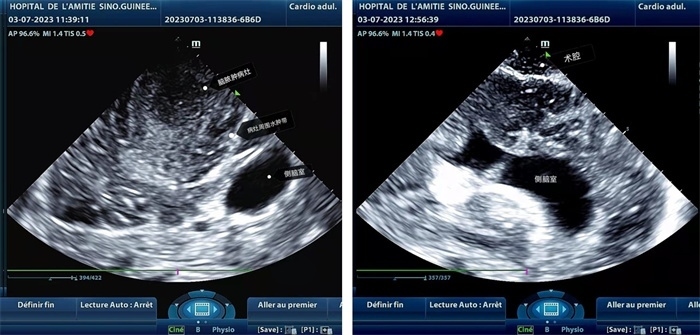

手術(shù)中,張國濱在超聲科顧秀娟的幫助下,運用顱腦術(shù)中超聲技術(shù),通過將一次性保護(hù)套的超聲探頭置于腦組織表面,實時觀察病變的位置和形態(tài),進(jìn)一步確認(rèn)最佳手術(shù)路徑。術(shù)中超聲顯示,病變位于左額頂葉,大小約為4x4x3cm,邊界清晰,呈囊實性,周邊腦組織水腫明顯。最終,病灶順利切除,診斷為腦膿腫,并通過超聲檢測確認(rèn)術(shù)腔無病變殘留、無出血,為患者術(shù)后恢復(fù)提供了良好的保障。

左圖顯示術(shù)中超聲見囊實性病變,大小約為4x4x3cm,病灶周圍腦組織水腫明顯;右圖為病灶切除后,術(shù)中超聲示術(shù)腔無病變殘留

左圖顯示術(shù)中超聲見囊實性病變,大小約為4x4x3cm,病灶周圍腦組織水腫明顯;右圖為病灶切除后,術(shù)中超聲示術(shù)腔無病變殘留。中國第二十九批援幾內(nèi)亞醫(yī)療隊供圖